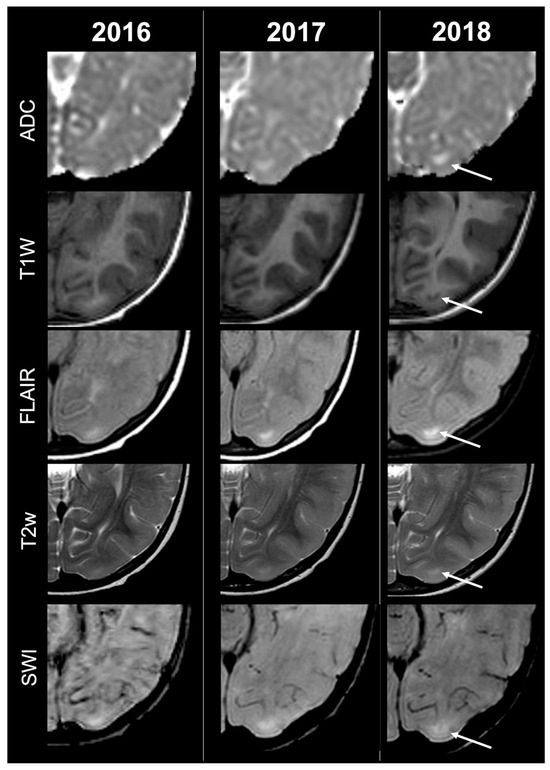

Cortical Tubers’ Transformation in Pediatric Patients Diagnosed with Tuberous Sclerosis Complex: A Retrospective Longitudinal MRI Analysis

Background: Cortical tubers (CTs) are hallmark brain lesions in tuberous sclerosis complex (TSC), historically considered stable in number over time; prior literature has correlated overall CT burden on magnetic resonance imaging (MRI) with disease severity. As longitudinal imaging studies assessing CTs’ evolution over time are lacking, we aim to investigate temporal changes in CTs—both in number and signal—on MRI in a cohort of pediatric TSC patients. Methods: A retrospective single-center analysis was conducted on 57 pediatric TSC patients who underwent longitudinal MRI studies in a 10-year span. Required MRI sequences included volumetric unenhanced T1-weighted, SWI, T2w and/or FLAIR. CTs were evaluated by two neuroradiologists and classified into five subtypes (A, B, C1, C2, D) according to signal characteristics. Statistical comparison was performed using t-tests. Results: Paired t-test analysis demonstrated a significant longitudinal increase in the overall number of CTs, rising from 16.11 ± 12.43 at baseline to 18.77 ± 13.29 at follow-up (mean difference = −2.67, 95% CI [−3.94, −1.39]; t (56) = 4.19; p < 0.0001), corresponding to a moderate effect size (Cohen’s d ≈ 0.56). When stratified by age, patients <2 years—representing the incompletely myelinated subgroup—showed a more pronounced increase in CT burden, from 19.46 ± 15.21 to 24.17 ± 15.75 (mean difference = −4.71, 95% CI [−7.37, −2.04]; t (23) = 3.65; p = 0.0013; d ≈ 0.75). In contrast, patients aged ≥2 years demonstrated a smaller but still significant increase, from 13.67 ± 9.45 to 14.85 ± 9.64 (mean difference = −1.18, 95% CI [−2.08, −0.28]; t (32) = 2.68; p = 0.0115; d ≈ 0.46). Direct comparison between the two subgroups using Welch’s two-sample t-test confirmed that the mean CT count in patients <2 years was significantly higher than in those ≥2 years (mean difference = 3.53 ± 1.36; t = 2.59; df = 28.4; p = 0.0075), with a large effect size (Cohen’s d ≈ 0.78). Type C1-C2 tubers evolved from pre-existing earlier-stage lesions, while most newly visible CTs over time were type A-B. Type D tubers remained rare and derived from earlier-stage CTs. Conclusions: Contrary to previous assumptions, CTs in pediatric TSC showed a tendency to increase in number and evolve in signal over time, thus challenging the notion of stability and suggesting dynamic behavior. Incomplete myelination in early infancy may impact MRI CTs detection by reducing contrast with surrounding brain tissue, potentially leading to their underestimation/misidentification. Full article

Show Figures

Figure 1